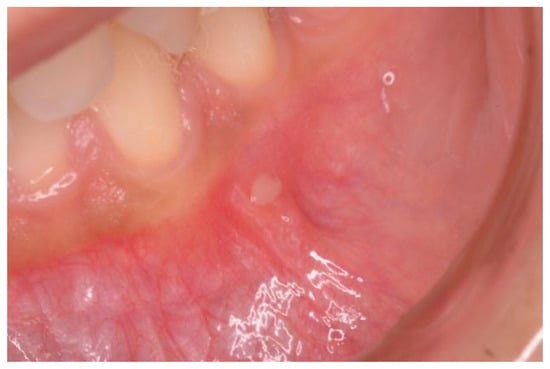

The color, type, and site of dental enamel defects were recorded and classified according to Aine classification [8,13]. According to Aine, enamel defects appear symmetrically and chronologically in the same anatomical groups of teeth in all four quadrants of dentition, while single and asymmetrical changes were regarded as highly unspecific to CD. Enamel hypoplasia, in particular, is characterized by a reduced deposition of the enamel matrix by the ameloblasts. This alteration is clinically featured by depressions or grooves on the surface of the tooth (Figure 2).

Figure 2. A case of enamel hypoplasia in a celiac disease (CD) patient.

Depending on the severity, it can vary from a mere change of color towards chalky white or gray and brownish, to areas of leakage of substances, up to severe cases of complete absence of enamel. Finally, the presence of atrophic glossitis (geographic tongue) was detected, which is characterized by glossodynia, atrophy of the filiform papillae, and erythematous areas on the back of the tongue.